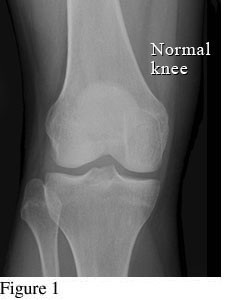

Hình ảnh so sánh giữa khớp bình thường và khớp bị thoái hóa khớp gối

Hình ảnh khớp gối trên phim X-quang: Khe khớp gần như bình thường, có thể có gai xương nhỏ.

Ở giai đoạn đầu tiên, khớp gối chưa có dấu hiệu bất thường cho thấy bị thoái hóa khớp gối. Bệnh nhân đi lại bình thường, chưa xuất hiện cơn đau khớp hoặc có thể chỉ đau khớp gối khi đứng lên ngồi xuống, ngồi xổm, lên xuống cầu thang. Khớp gối cũng chưa bị sưng và không biến dạng. Nếu chụp thêm MRI có thể thấy khớp gối gần như bình thường.